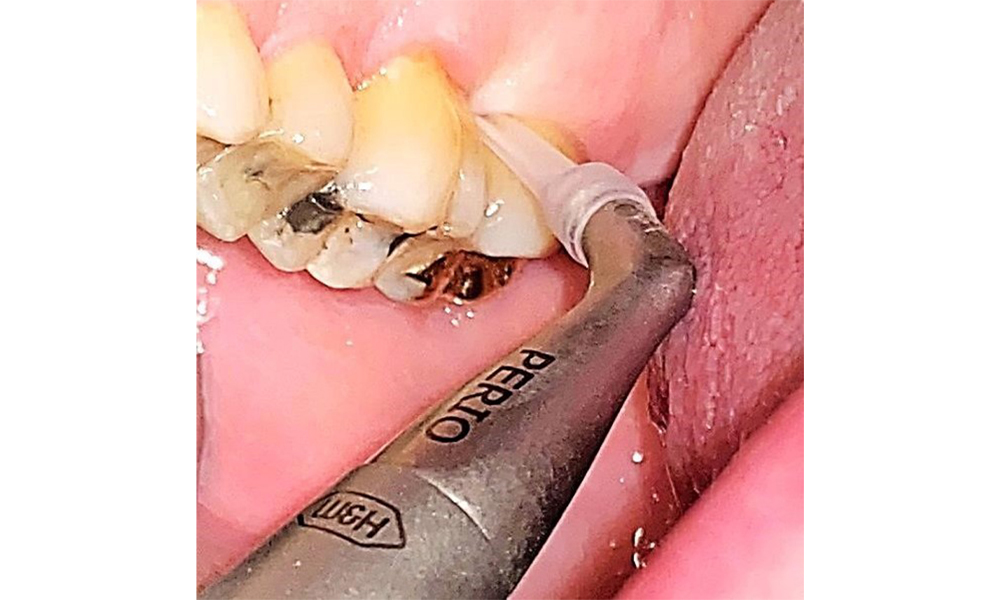

Няма ограничения по отношение на избора на методи за измерване. Редовната супрагингивална и субгингивална инструментация е от съществено значение за предотвратяване на прогресията на заболяването поради вече съществуващия пародонтит и високия риск от рецидив. От общомедицинска гледна точка няма ограничения върху избора на инструменти за механично отстраняване на биофилм и отстраняването трябва да се извършва според нуждите. Твърдата и минерализирана плака, като зъбен камък и конкременти, трябва да се отстранява с помощта на ръчни инструменти или ултразвукови скалери (фиг. 9) (8, 9).